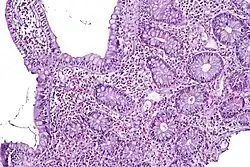

Enteritis, a major complication of a Campylobacter jejuni infection, results in inflammation as pictured above, in which eosinophil aggregation occurs.

Campylobacteriosis is an infectious disease caused by bacteria of the genus Campylobacter. In most patients presenting with campylobacteriosis, symptoms develop within two to five days of exposure to the organism and illness typically lasts seven days following onset.[24] Infection with C. jejuni typically results in enteritis, or inflammation of the small intestine, which is characterized by abdominal pain, voluminous diarrhea (often bloody), fever, and malaise. Individuals infected with this bacteria can experience a prodromal phase of symptoms for the first 1 to 3 days, in which the more severe portion of the disease occurs. The prodromal phase presents with symptoms including rigors, high fever, body aches, and dizziness. Other than the prodromal phase, the acute diarrheal phase of enteritis usually lasts around 7 days, however abdominal pain can persist for weeks afterward.[3] The disease is usually self-limiting; however, it does respond to antibiotics. Severe (accompanying fevers, blood in stools) or prolonged cases may require erythromycin, azithromycin, ciprofloxacin, or norfloxacin. Fluid replacement via oral rehydration salts may be needed and intravenous fluid may be required for serious cases.[24] Possible complications of campylobacteriosis include Guillain–Barré syndrome and reactive arthritis.[3]